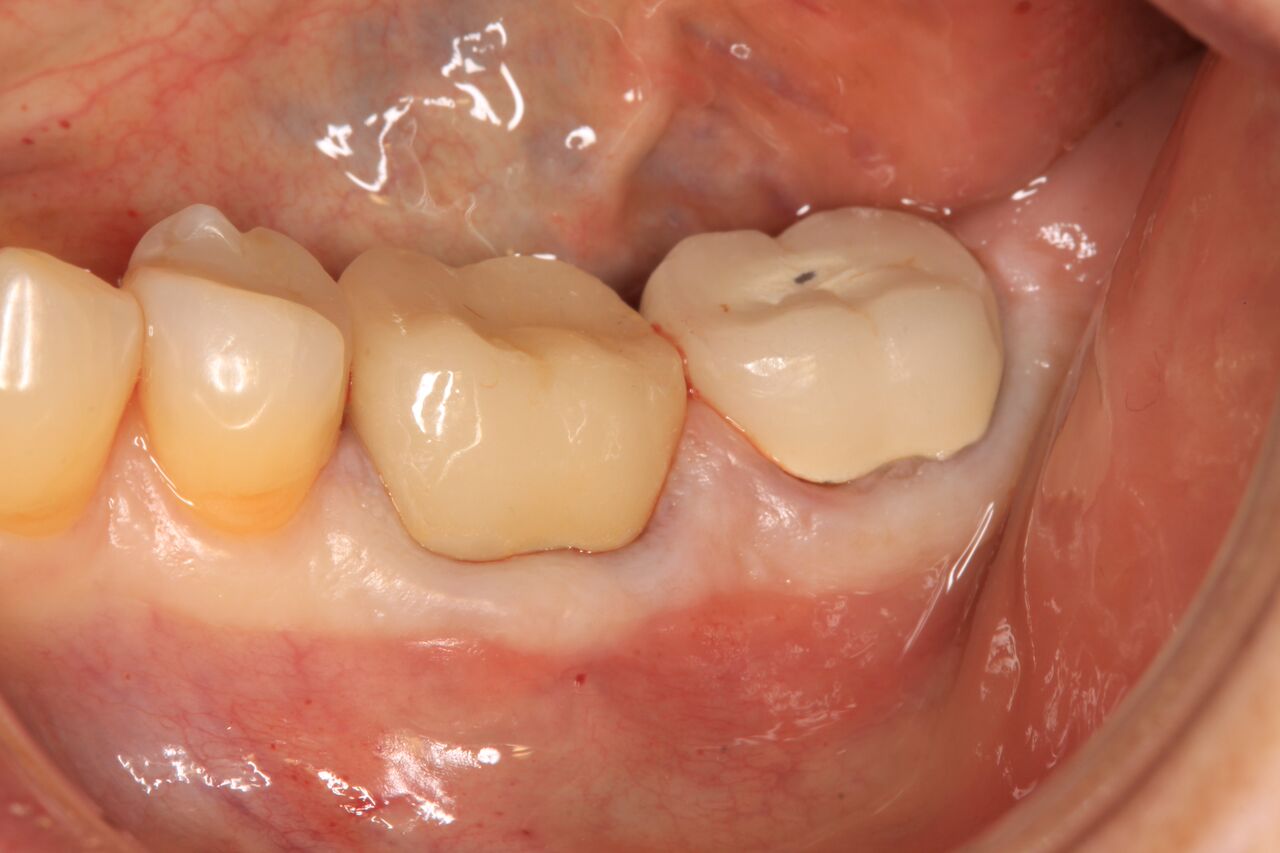

The patient was prescribed antibiotics and analgesics and instructed in postoperative care particular to immediately provisionally restored implants. At 6 months, integration was confirmed (Figure 14) and the patient returned to her dentist for restoration. The implants were restored with individual cement-retained crowns with a platform shift for No. 12 restoration from the 6-mm diameter of the implant to a 5-mm diameter of the final restoration (Figure 15 and Figure 16).

(15.) Clinical view of final individual crowns on Nos. 12 and 13.

Figure 15